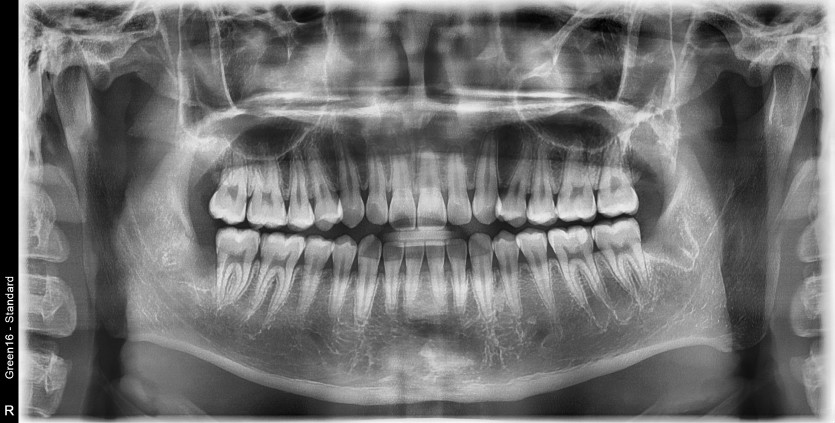

#28,29(과잉치),38 사랑니 발치

구강 외과 전문의가 당일 발치했습니다.